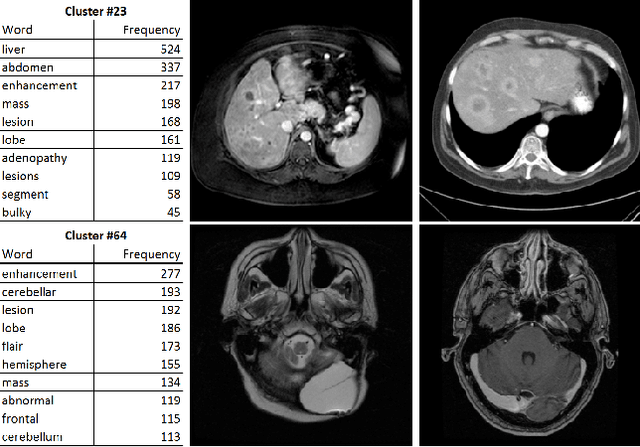

Abstract:Obtaining semantic labels on a large scale radiology image database (215,786 key images from 61,845 unique patients) is a prerequisite yet bottleneck to train highly effective deep convolutional neural network (CNN) models for image recognition. Nevertheless, conventional methods for collecting image labels (e.g., Google search followed by crowd-sourcing) are not applicable due to the formidable difficulties of medical annotation tasks for those who are not clinically trained. This type of image labeling task remains non-trivial even for radiologists due to uncertainty and possible drastic inter-observer variation or inconsistency. In this paper, we present a looped deep pseudo-task optimization procedure for automatic category discovery of visually coherent and clinically semantic (concept) clusters. Our system can be initialized by domain-specific (CNN trained on radiology images and text report derived labels) or generic (ImageNet based) CNN models. Afterwards, a sequence of pseudo-tasks are exploited by the looped deep image feature clustering (to refine image labels) and deep CNN training/classification using new labels (to obtain more task representative deep features). Our method is conceptually simple and based on the hypothesized "convergence" of better labels leading to better trained CNN models which in turn feed more effective deep image features to facilitate more meaningful clustering/labels. We have empirically validated the convergence and demonstrated promising quantitative and qualitative results. Category labels of significantly higher quality than those in previous work are discovered. This allows for further investigation of the hierarchical semantic nature of the given large-scale radiology image database.